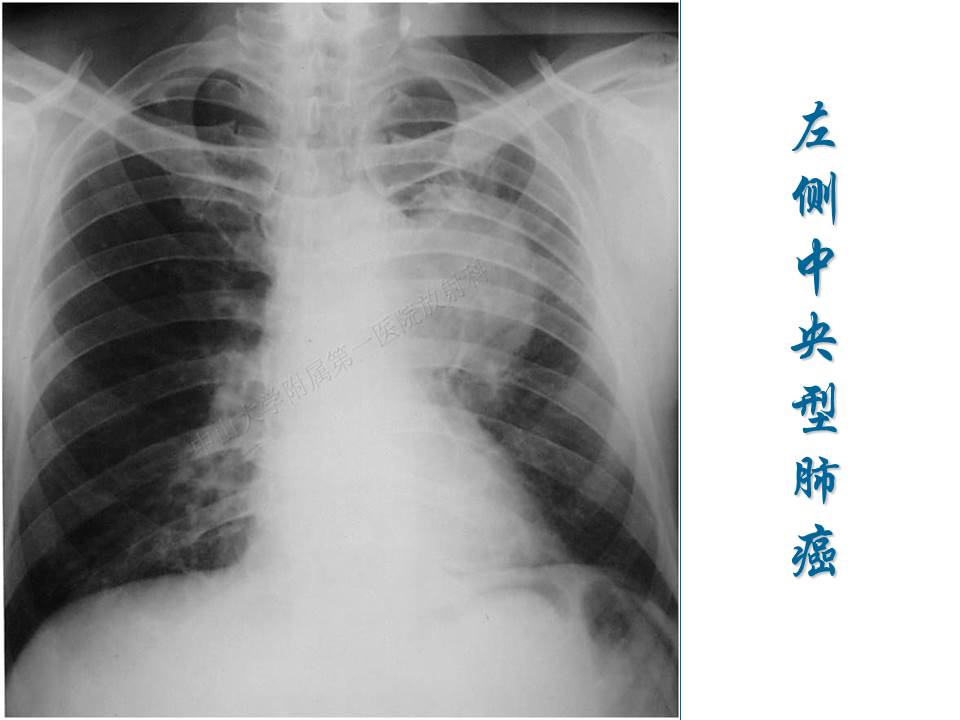

支气管肺癌的影像学诊断